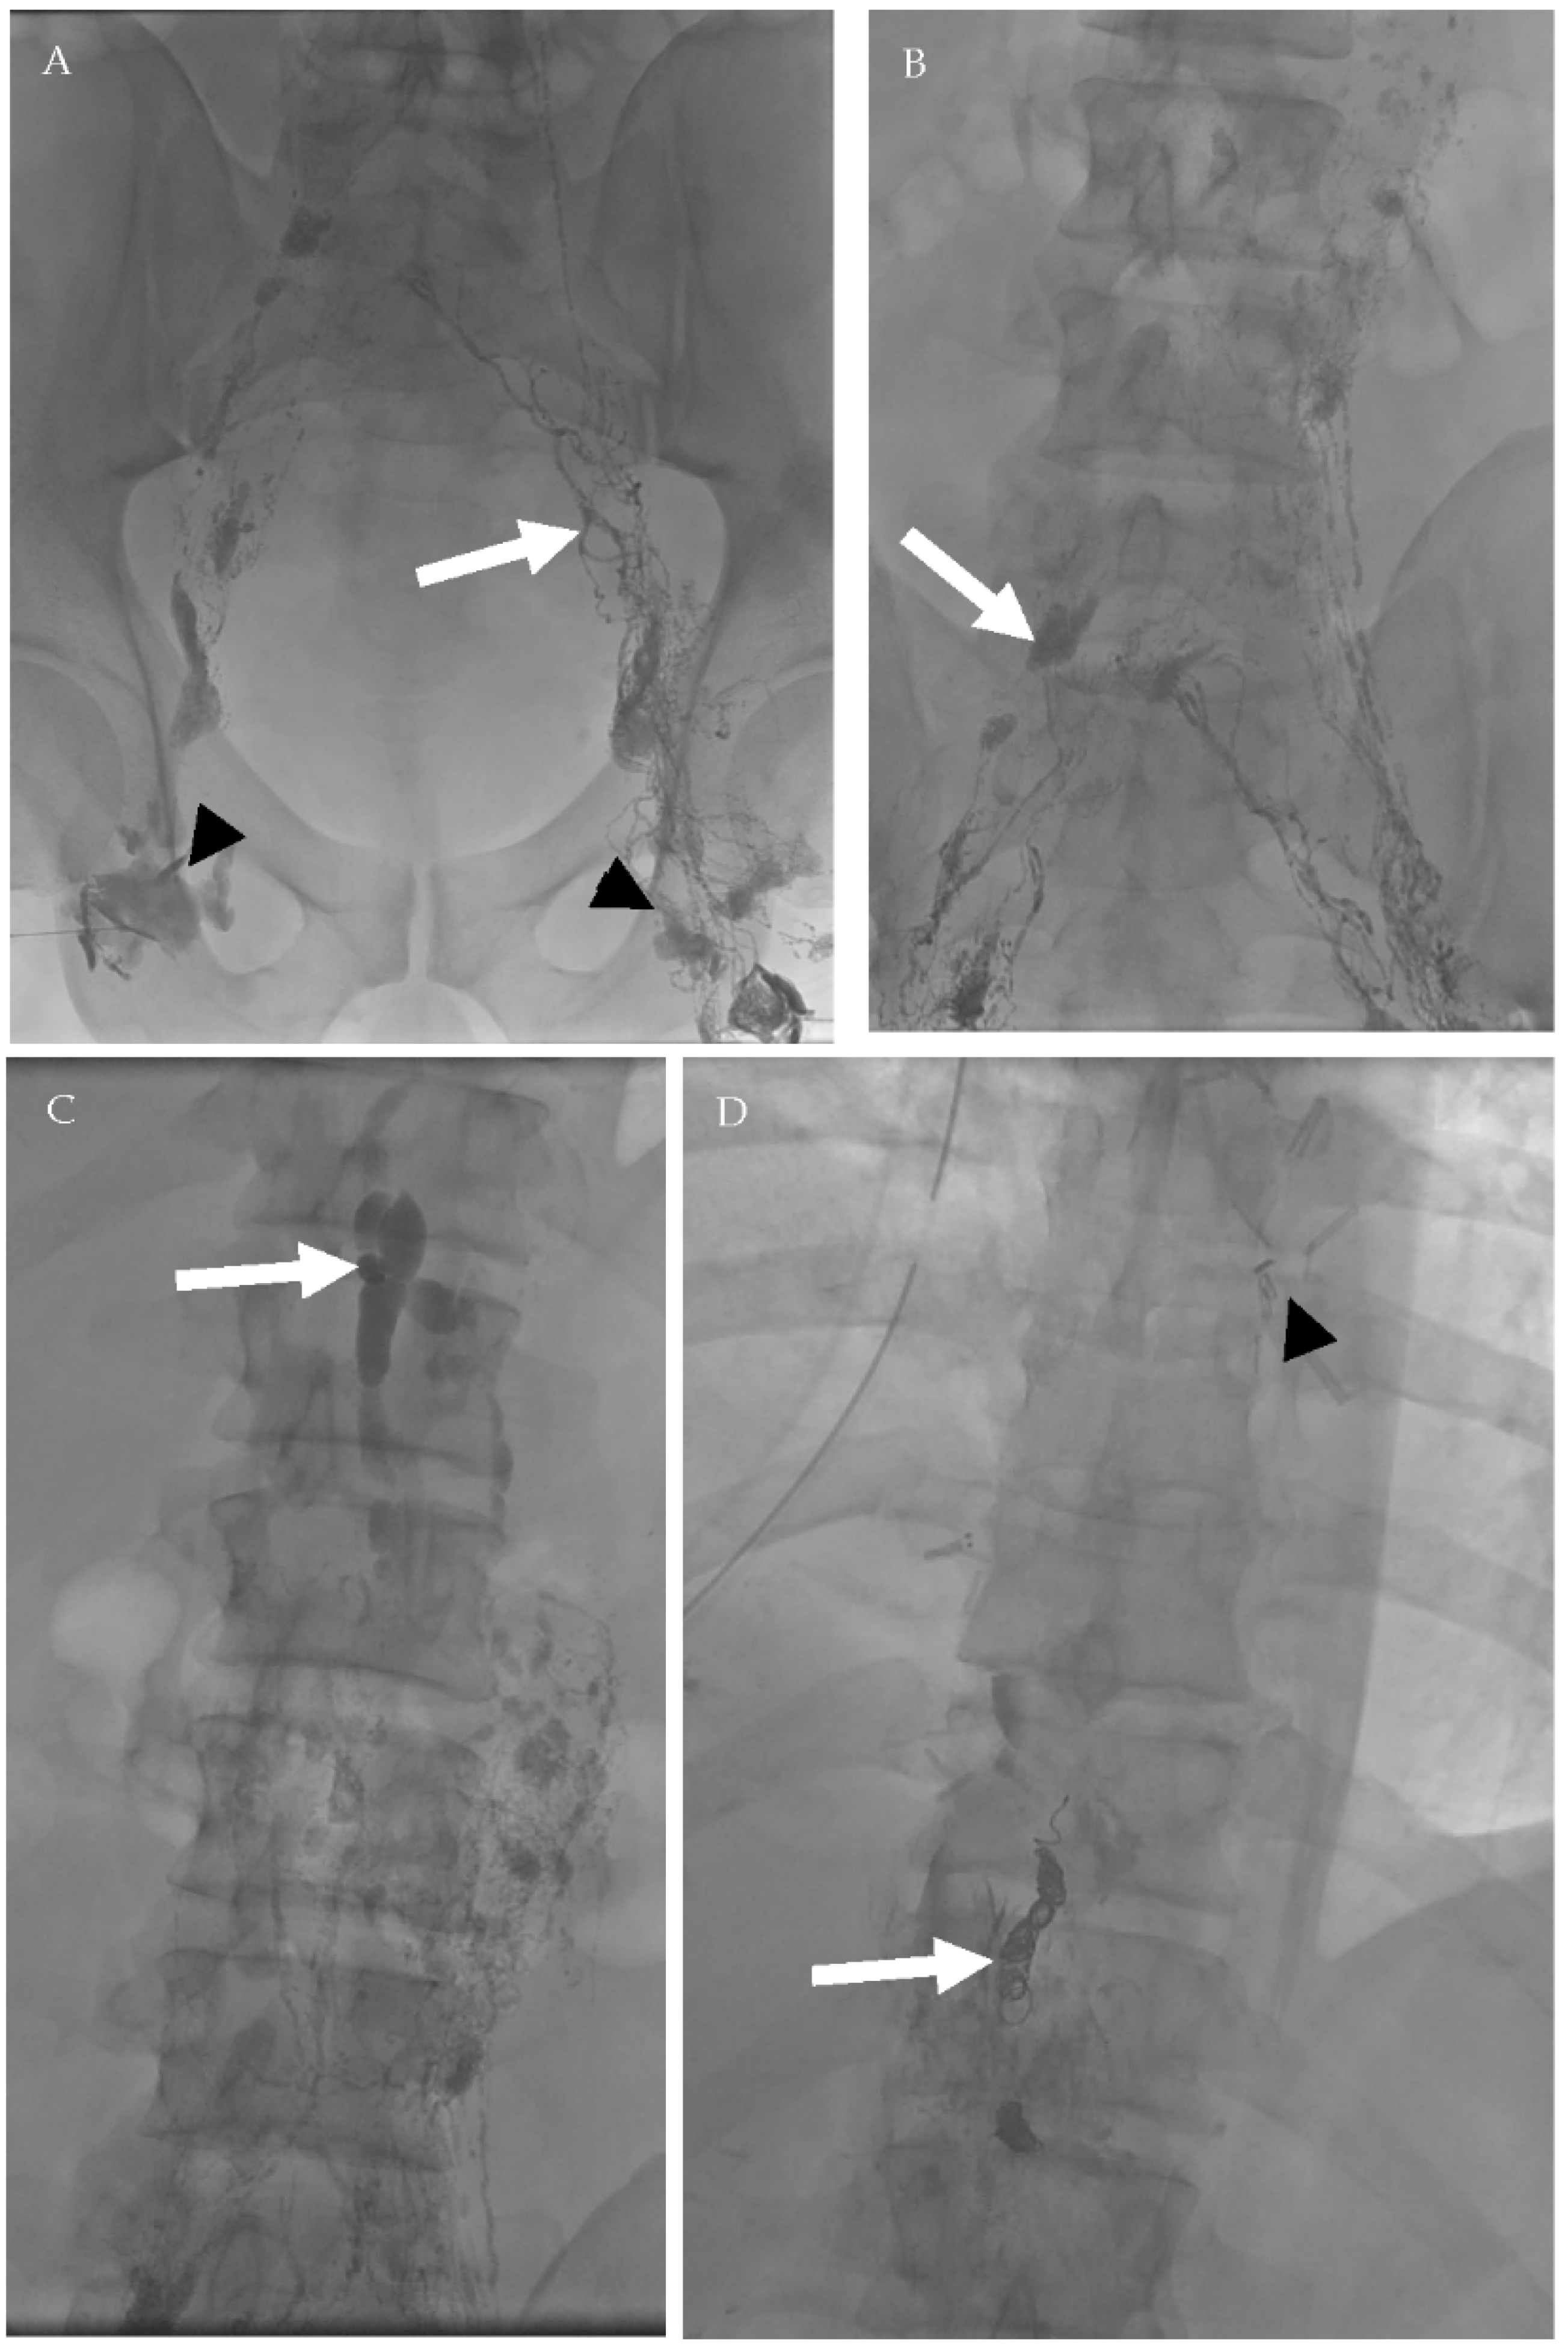

4.2.1. Conventional Lymphangiography (CL)